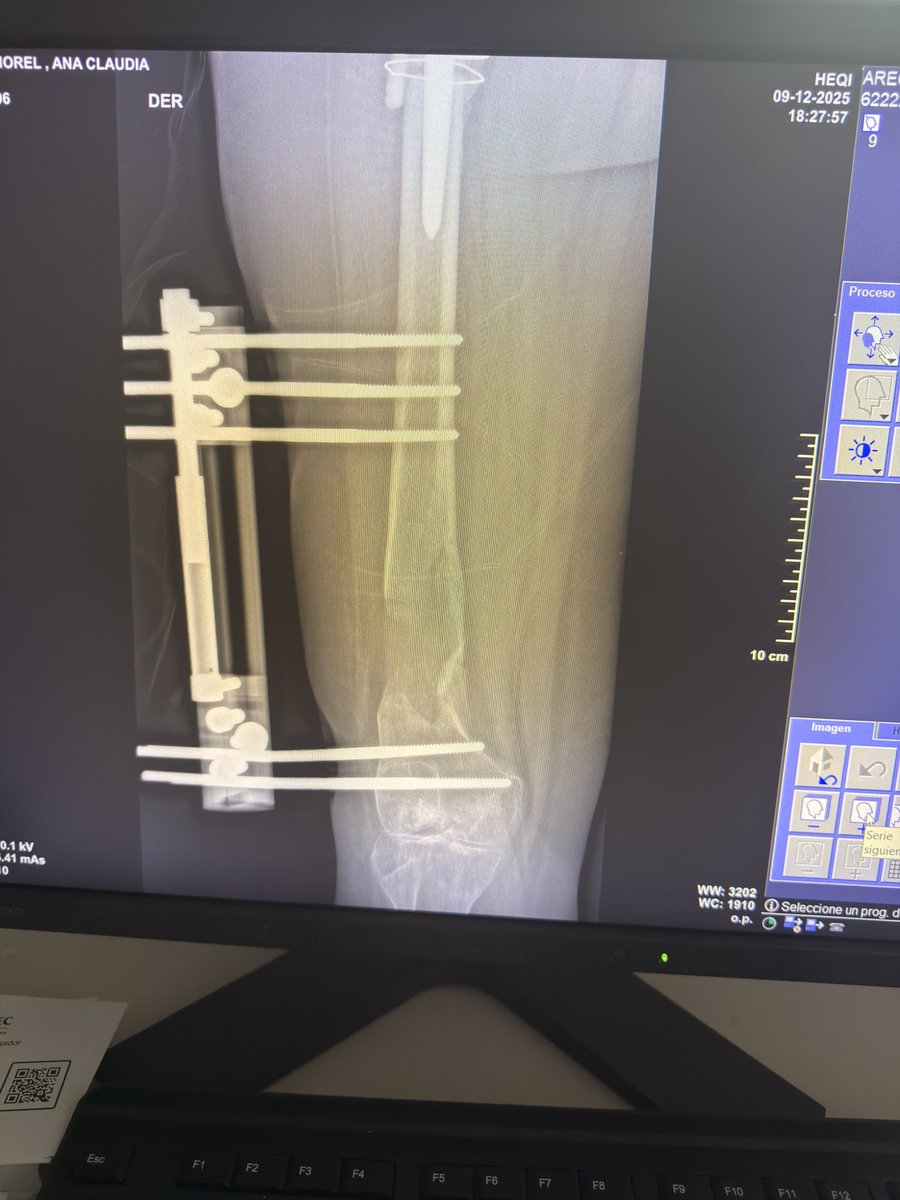

Essas sao as minhas radiografias, da pra ver o meu nome. Como o joelho nao esta dobrando (ja foram 5 cirurgias) eu nao consigo dirigir e ir com frequência nos correios e por isso uma menina se dispôs a fazer uma CEG de todas as minhas coisas ✨🩵 Estarei passando o contato dela.